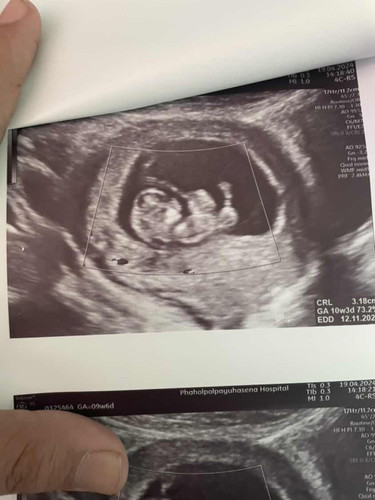

ท้อง9สัปดาห์4วัน อันตร้าซาวน์ผนังหน้าท้องลูกเรายังไม่ปิด แม่บ้านไหนเคยเจอแบบนี้บ้างคะ ตอนนี้เราทั้งเครียดทั้งเศร้า มีโอกาศที่จะปิดไหมคะ 🥺